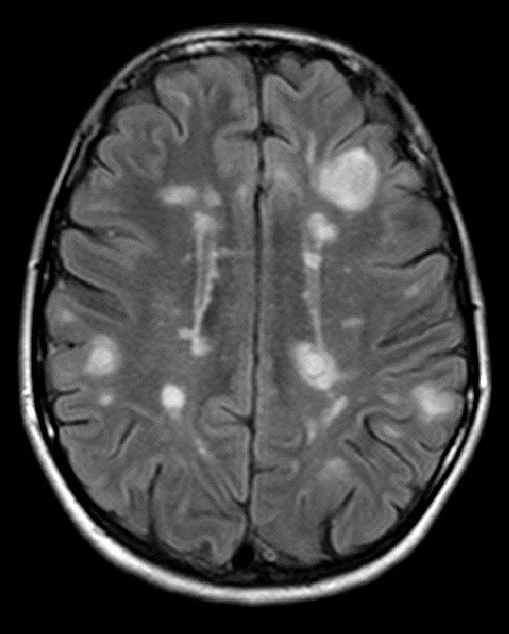

Очаги рассеянного склероза в головном мозге на снимке МРТ